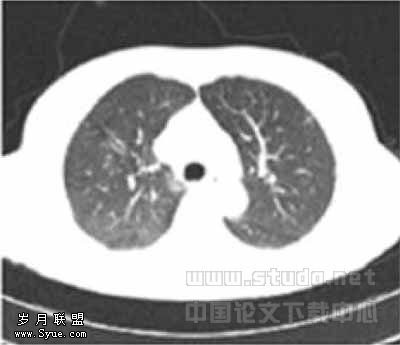

49例图像中,LD1与LD2扫描各有2例图像质量为良好(图1,2),其余均为优秀(图3,4),1例LD扫描图像比SD扫描图像清晰,原因是LD扫描时患者吸气充分而SD扫描时患者吸气不足。

图1,2分别为同一层面的常规剂量与低剂量CT,可见少量伪影,不影响观察肺结节图3,4分别为同一层面的常规剂量与低剂量CT图像,示未见伪影图3示小于5mm肯定肺结节(→?)和模糊肺结节(←?),图4分别显示为肯定(→?)、未见(←?)